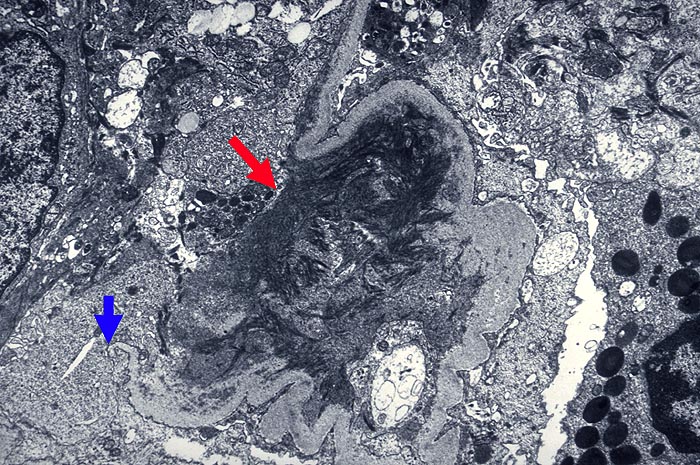

Extrakapillär betonte Glomerulonephritis: Schlingenruptur

Die periphere glomeruläre Basalmembran ist an einer Stelle unterbrochen. Im Schlingenlumen Fibrinstränge.

Glomeruli mit Halbmond zeigen immer Schlingenrupturen (wenn man in Serienschnitten danach sucht!) im Frühstadium mit Fibrinexsudation in den Kapselraum.